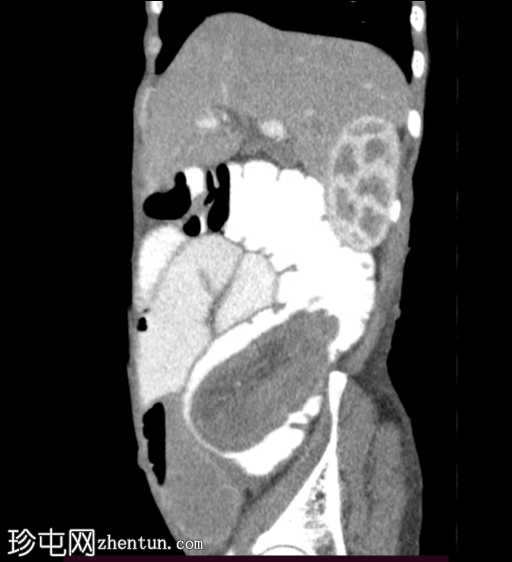

矢状位增强扫描

动脉期

回肠肠袢套入盲肠,形成肠套叠形态,轴位和纵位图像分别可见靶征和腊肠征或假肾征。